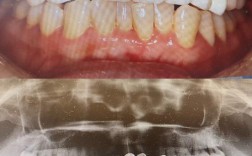

矫正牙齿的本质是牙齿在牙槽骨中的移动,这个过程必然伴随疼痛,25岁的骨骼已发育完全,牙槽骨密度更高,牙齿移动的阻力比青少年更大,因此疼痛感可能更强烈且持久,初期戴牙套后的1-2周,牙齿对咬合、刷牙、甚至说话都会产生敏感酸痛,有人只能喝粥、吃流食,体重下降5公斤;每次调整弓丝后,疼痛会再次加剧,持续3-5天才能缓解,更让人难以忍受的是,牙套边缘可能摩擦口腔黏膜,导致反复发作的溃疡,即使使用正畸蜡也只能暂时缓解,有矫正者回忆,曾因溃疡严重到无法正常进食,只能靠打营养液维持,最终不得不暂停矫正一周,牙齿移动过程中可能出现暂时性松动,让矫正者时刻担心“牙齿会不会掉”,这种对口腔健康的焦虑,进一步放大了痛苦体验。

矫正牙齿意味着与许多美食“告别”,硬的、黏的、脆的食物(如坚果、牛肉干、口香糖)都可能损坏牙套或导致托槽脱落,需要格外小心,有矫正者曾因忍不住吃了一块排骨,导致托槽脱落,紧急预约医生调整,不仅花费额外费用,还延长了矫正周期;还有人因吃火锅时牙套上沾满辣椒碎,在社交场合尴尬不已,口腔清洁难度大幅增加,牙套周围容易残留食物残渣,需要使用正畸牙刷、牙缝刷、冲牙器等工具,刷牙时间从2分钟延长到20分钟,稍有不慎就会引发龋齿、牙龈炎,有受访者表示,矫正期间曾因清洁不到位导致牙齿脱矿,出现白斑,至今未能完全恢复,这让她对“为了变美反而损伤牙齿”感到深深后悔。